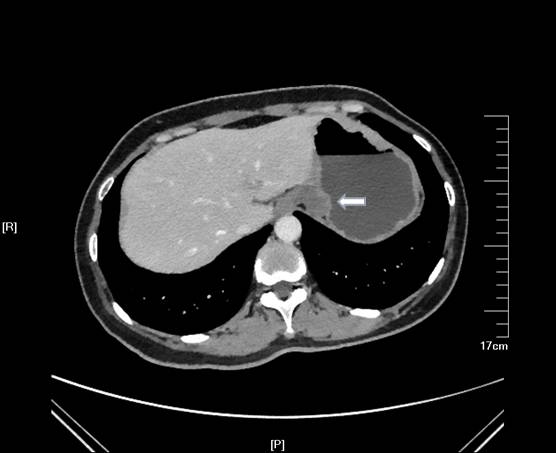

EUS考虑血管瘤,动员患者在我院复查增强CT,常规水平成像可见胃底软组织影(下图 白色箭头)。

但经冠状位和矢状位重建放大后证实来源于肝左叶近膈顶部外生性血管瘤压迫胃底(下图A-B 黄色箭头处)。